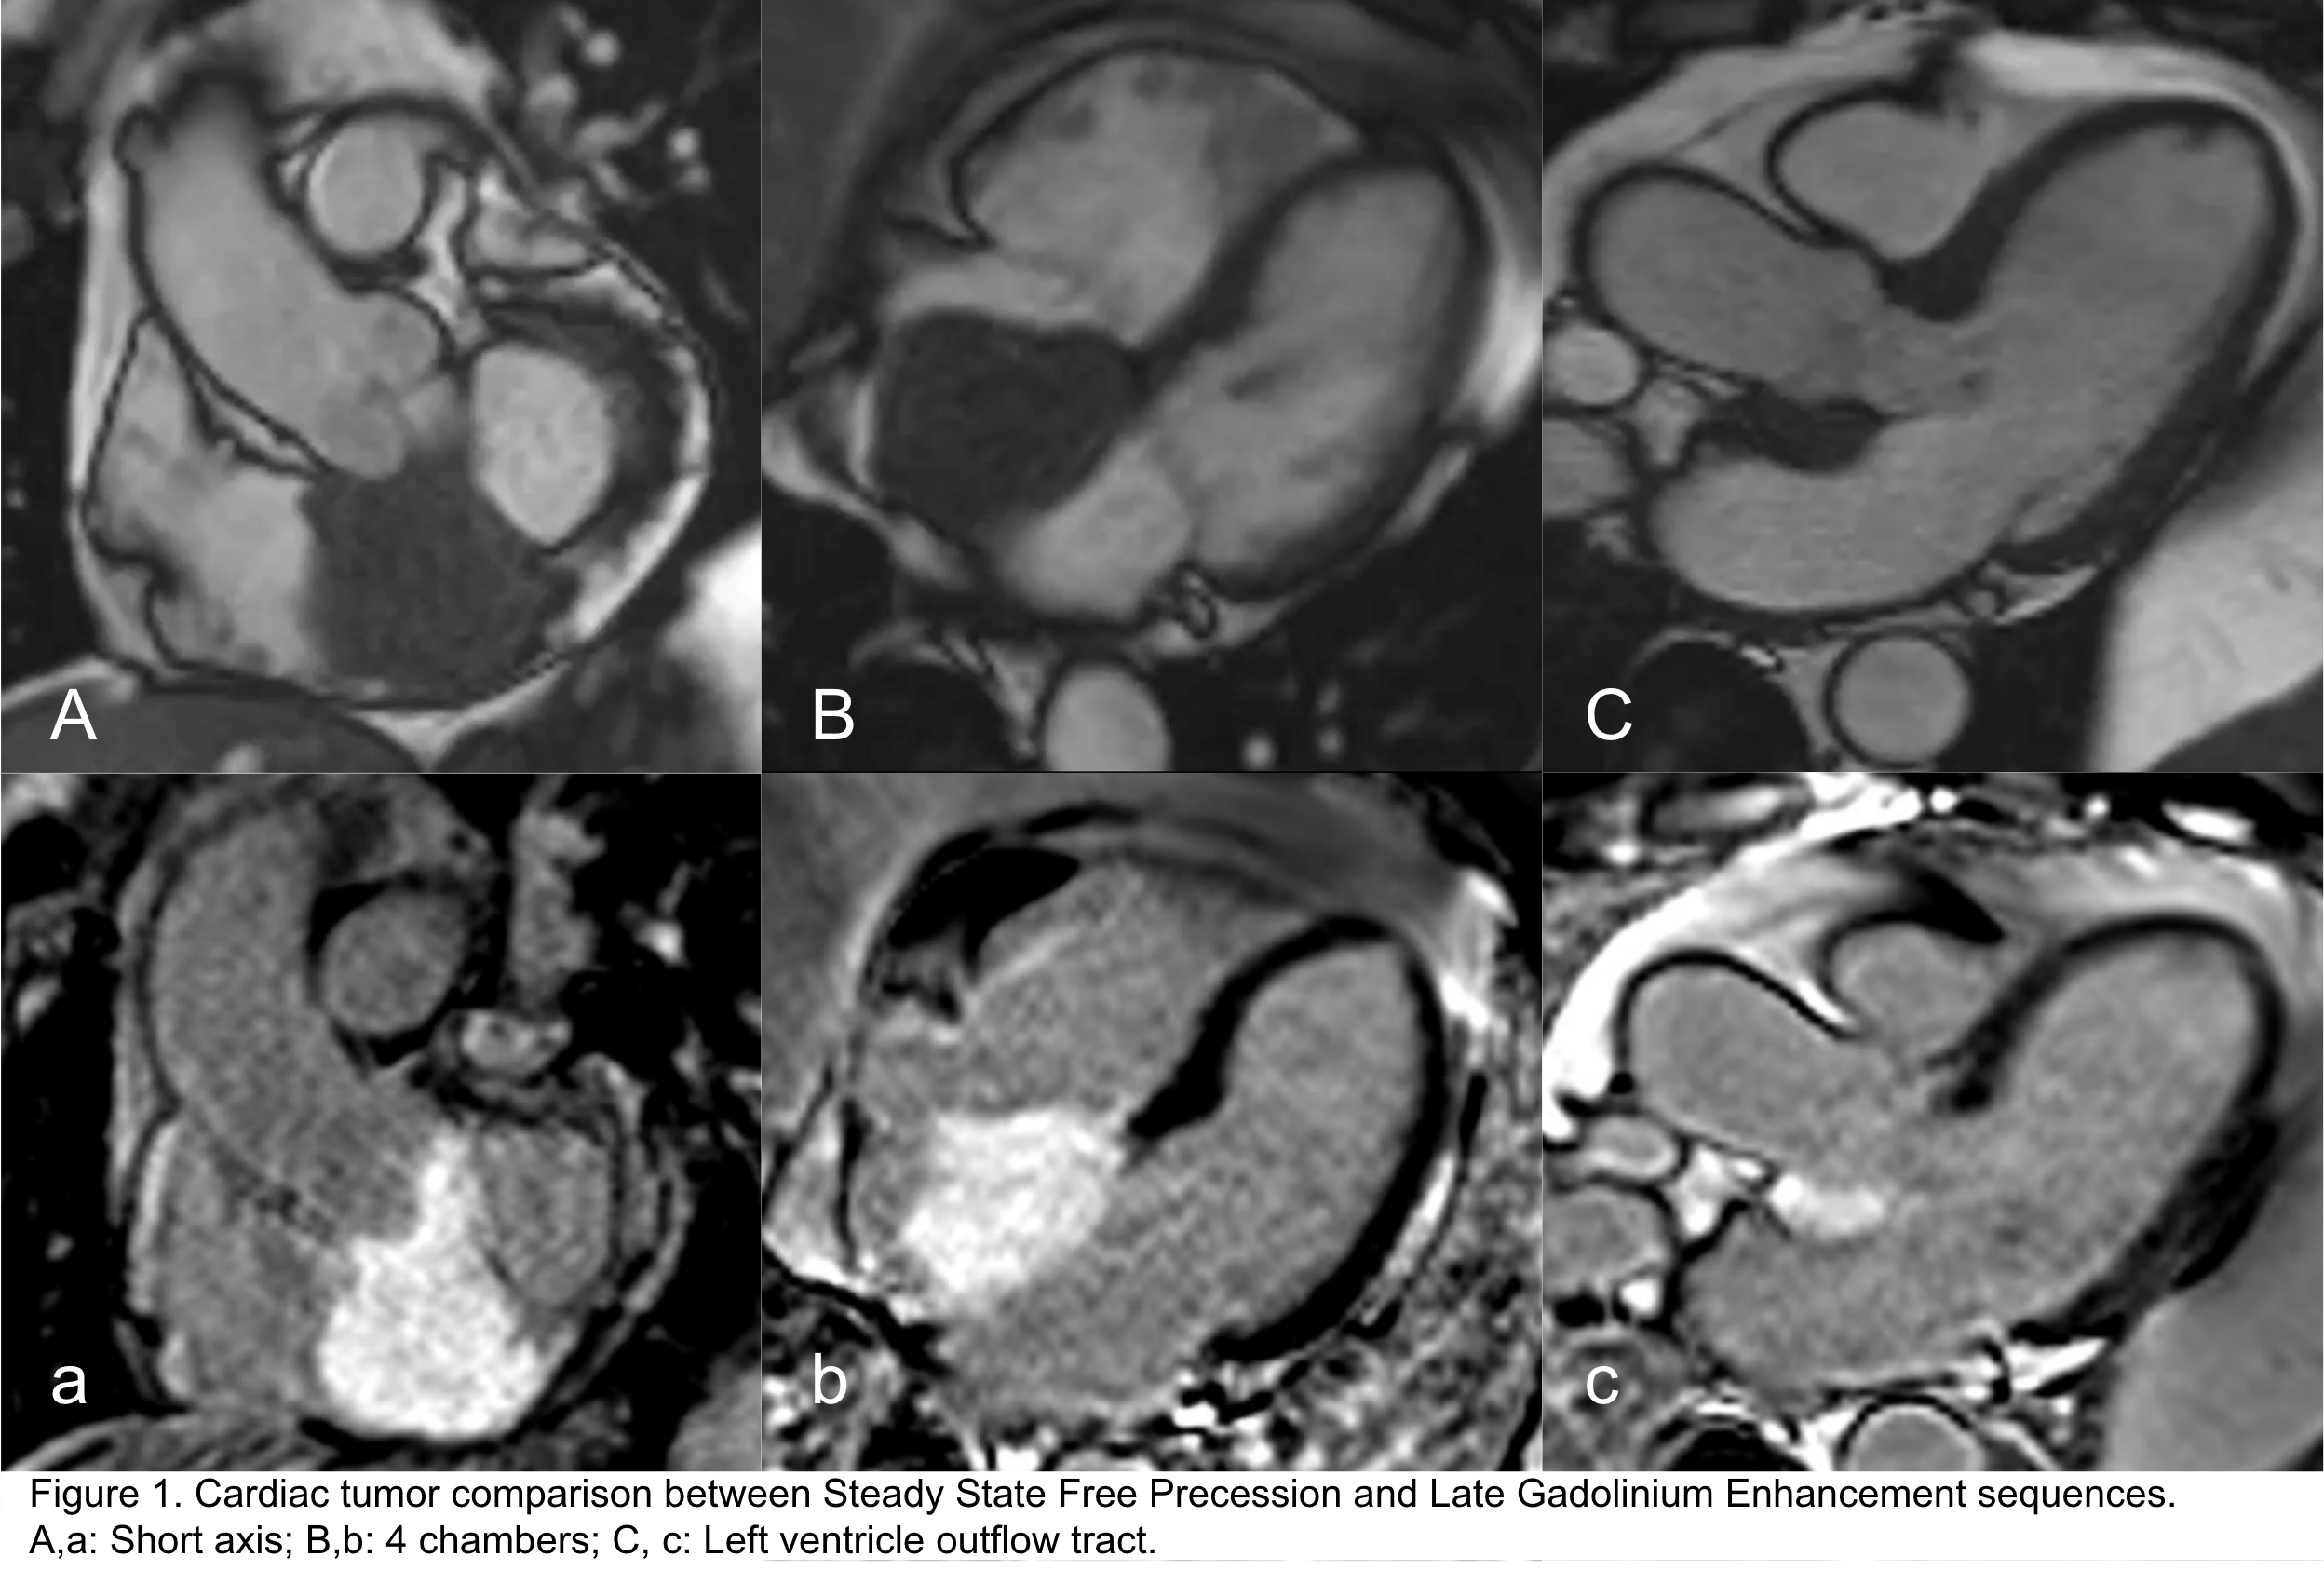

Perfusion sequences